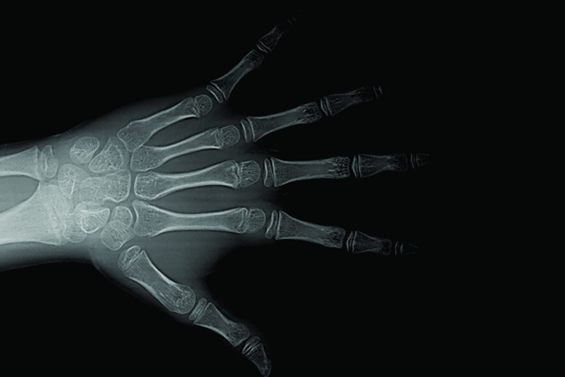

Radiografia Carpal

A estimativa da idade óssea através da radiografia carpal é frequentemente utilizada para avaliar desordens no crescimento em pacientes pediátricos, sendo possível identificar se o seu crescimento evoluiu.